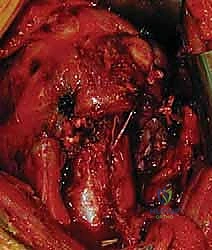

عندما تكون الكسور معقدة، نازحة بشدة، أو متعددة الأجزاء، يصبح التدخل الجراحي أمراً حتمياً لضمان شفاء العظم في وضعه التشريحي الصحيح واستعادة حركة الكتف. يقدم الأستاذ الدكتور محمد هطيف أحدث الخيارات الجراحية العالمية في صنعاء:

1. الرد المفتوح والتثبيت الداخلي (ORIF - Open Reduction and Internal Fixation)

هذا هو المعيار الذهبي لعلاج معظم الكسور النازحة (جزأين أو ثلاثة أجزاء، وبعض كسور الأربعة أجزاء لدى الشباب). يقوم الدكتور هطيف بفتح الكتف، وإعادة ترتيب الشظايا العظمية بدقة متناهية (الرد المفتوح)، ثم تثبيتها باستخدام شرائح معدنية تشريحية ذاتية القفل (Locking Plates - PHILOS) ومسامير.